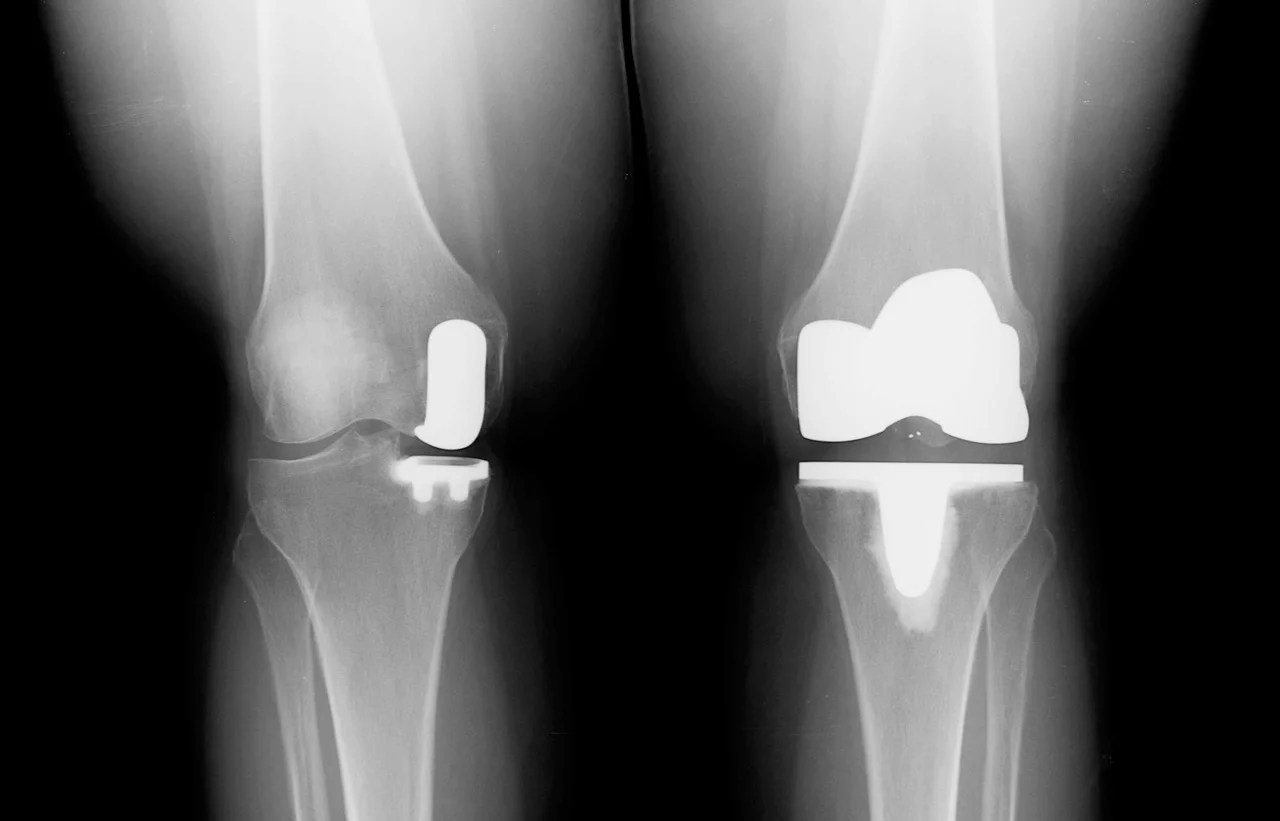

From www.reddit.com

Before/After my partial knee replacement surgery. You can see the bone When Can I Kneel After Partial Knee Replacement The short answer is yes! The authors conclude that education and supervised intervention after a partial knee replacement can make a difference. Can you kneel after a knee replacement? Resuming daily activities too soon. Read this blog written by a health professional student to learn why it is safe to kneel after a knee. The authors conclude that education and. When Can I Kneel After Partial Knee Replacement.